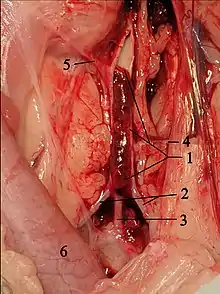

Clinically, cats with hypertrophic cardiomyopathy commonly have a systolic anterior motion (SAM) of the mitral valve (see graphic).[65] Cats with severe HCM often develop left heart failure (pulmonary edema; pleural effusion) because of severe diastolic dysfunction of the left ventricle. They may also develop a left atrial thrombus that embolizes, most commonly, to the terminal aorta creating acute pain and rear limb paralysis (see below). Sudden death can also occur but appears to be uncommon.[66][67]